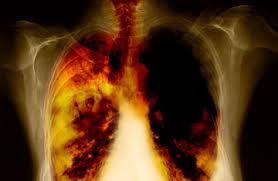

2. Lung Cancer

Lung cancer US distribution